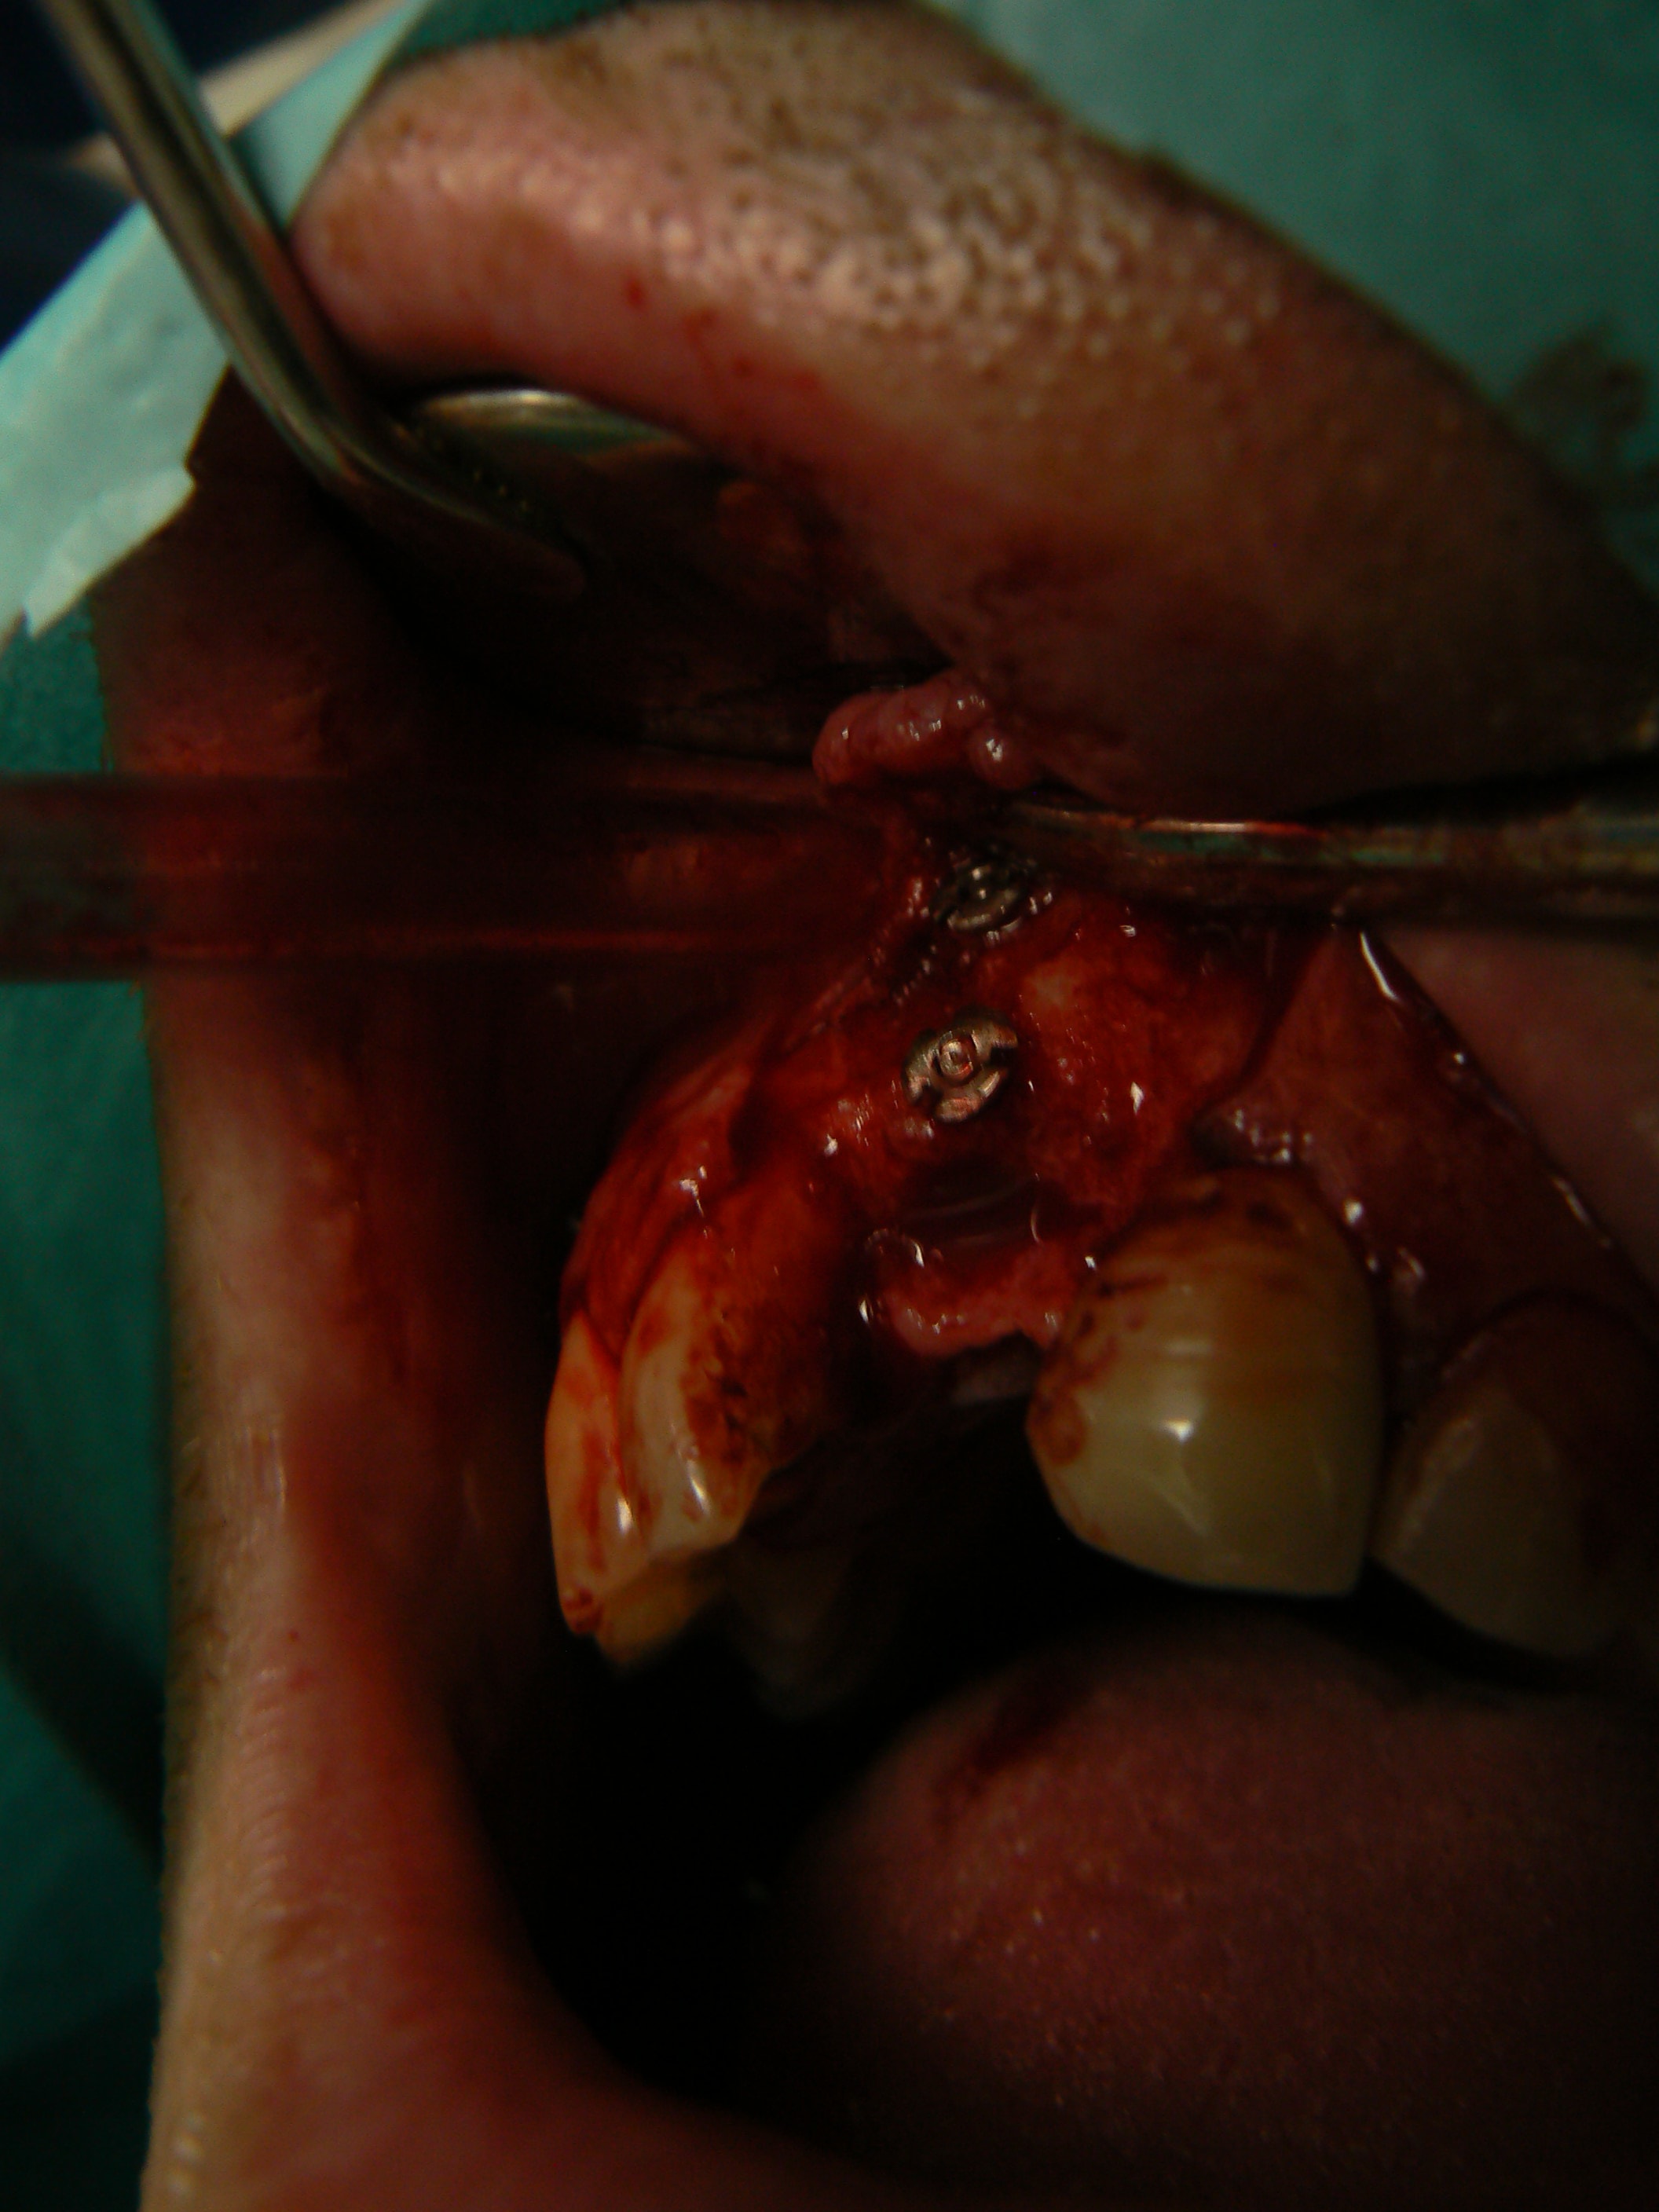

J'ai simplement peur que les vis de transfixation du greffon ne puissent provoquer son décollent au moment de leur dépose. En effet si de l'os vient se recréer entre les trois tétons, lors du dévissage ça peut provoquer un mouvement du greffon.

Bravo

> Ci joint cas avec biobank, très bonne stabilité et consistance a la réouverture

> a 9 mois.